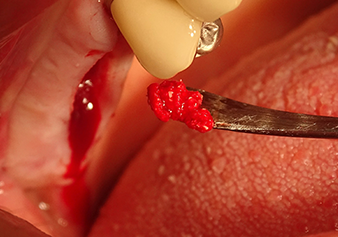

После промежуточного контроля (рис. 4) был проведен еще один этап подготовки (рис. 5). За тем, с помощью гидравлического инструмента Z35P мембрана была поднята в нужное положение (рис. 6 и 7). Далее, следовала дальнейшая пьезохирургическая подготовка ложа для имплантата, завершенная с помощью ротационного бора и лопаточной фрезы до диаметра имплантата 4,8 мм. Перед установкой имплантата под мембрану Шнейдера был введен аугментационный материал (размер частиц около 0,8-1,6 мм) (рис. 8).

The fibrous membrane is raised into its final position

Рис.6: Затем инструмент Z35P вводится периодически и активируется с настройками 100%/50%. В результате фиброзная мембрана поднимается в конечное положение.